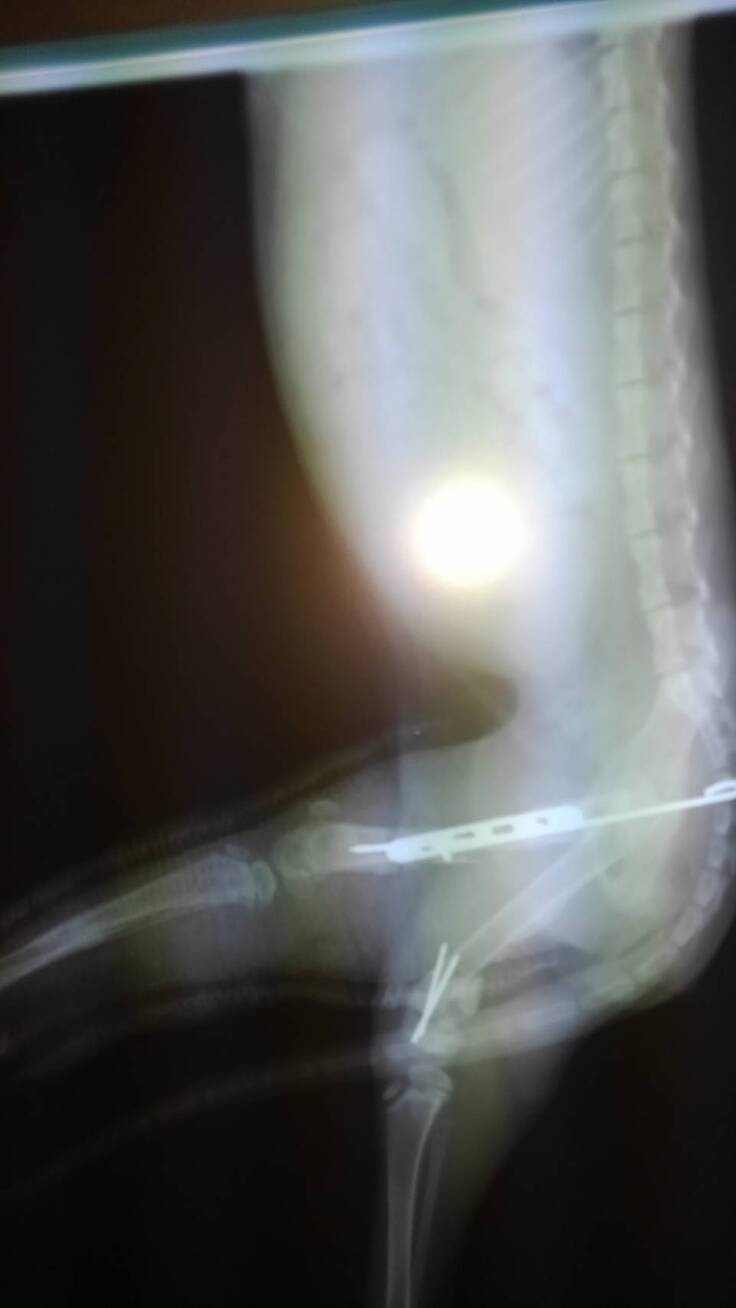

①初診9/25(日曜日)A動物病院

子猫を保護した9/25は日曜日だったので友人johnの地元(宜野湾市)に開いている動物病院が無く、ようやく探して嘉手納町のA動物病院へ連れて行きレントゲン撮影~両後ろ足の大腿骨が折れていたものの幸い緊急を要する症状が無かったので、自宅へ連れて帰り夜中一睡もせず看病したそうです。

(レントゲン写真と診療明細書はA動物病院から許可を得て掲載しています。)

②保護~2日目9/26(月曜日)B動物病院

保護した翌日、友人johnの地元かかりつけ病院で再度レントゲン撮影~やはり両後ろ足大腿骨が折れていた。病院の都合で直ぐに手術できないとの事、手術日の打ち合わせと抗生剤など簡単な治療~その日は子猫を自宅に連れて帰った。

右後肢大腿骨骨幹はプレートで固定、左後肢大腿骨遠位端はクロスピンで固定。

(レントゲン写真はB動物病院から許可を得て掲載しています。)